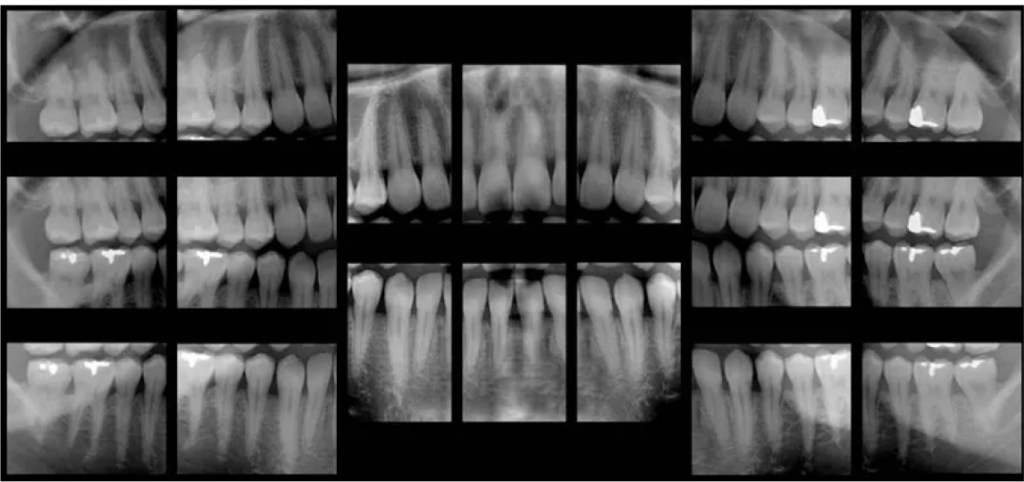

Dental X-rays enable dentists to see decay inside teeth that would not be visible to the naked eye. This allows us to act earlier against cavities, which is much better for the teeth. Thanks to advances in technology, there is now a safer way to take these images.

Film X-rays have been used in dentistry for decades. In the past few years, many forward-thinking dentists like Dr. Hicken have invested in digital X-ray technology. Film X-rays cost a bit less than digital X-rays but the increased exposure to film X-rays is more harmful to a patient’s overall health. Our digital X-ray emits as much as 85 percent less radiation than traditional X-ray technology.

Digital X-rays are one of the most important new advances in our office. We are not only able to reduce your exposure to radiation but also increase the diagnostic proficiency. In addition to increased diagnostics, we reduce the amount of harmful chemicals and other waste materials associated with traditional X-ray technology. The reduction in waste was a big consideration when deciding to invest in digital technology. We pride ourselves in being environmentally responsible.